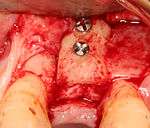

- Soft tissue reflection: An incision is made over the crest of bone, splitting the thicker attached gingiva roughly in half so that the final implant will have a thick band of tissue around it. The edges of tissue, each referred to as a flap are pushed back to expose the bone. Flapless surgery is an alternate technique, where a small punch of tissue (the diameter of the implant) is removed for implant placement rather than raising flaps.

- Drilling at high speed: After reflecting the soft tissue, and using a surgical guide or stent as necessary, pilot holes are placed with precision drills at highly regulated speed to prevent burning or pressure necrosis of the bone.

- Drilling at low speed: The pilot hole is expanded by using progressively wider drills (typically between three and seven successive drilling steps, depending on implant width and length). Care is taken not to damage the osteoblast or bone cells by overheating. A cooling saline or water spray keeps the temperature low.

- Placement of the implant: The implant screw is placed and can be self-tapping,[18](pp100–102) otherwise the prepared site is tapped with an implant analog. It is then screwed into place with a torque controlled wrench[19] at a precise torque so as not to overload the surrounding bone (overloaded bone can die, a condition called osteonecrosis, which may lead to failure of the implant to fully integrate or bond with the jawbone).

- Tissue adaptation: The gingiva is adapted around the entire implant to provide a thick band of healthy tissue around the healing abutment. In contrast, an implant can be "buried", where the top of the implant is sealed with a cover screw and the tissue is closed to completely cover it. A second procedure would then be required to uncover the implant at a later date.